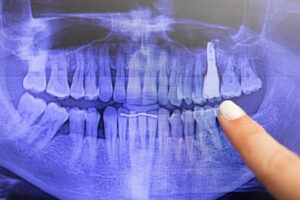

上の奥歯の上方には「上顎洞」と呼ばれる副鼻腔が存在しています。その部分は大きな空洞となっており、上の歯の歯根と近接しています。人によっては、上の奥歯の歯根が上顎洞に入り込んでいるような状態になっていることもあります。そのため、上の奥歯の部分にインプラントをしようとしても、インプラントを埋めるのに十分な骨の厚さがない、ということは決して珍しくありません。しかも、歯を失っている場合、歯周病などでさらに骨が破壊されていることが多いため、より一層インプラントをすることが難しくなってしまいます。